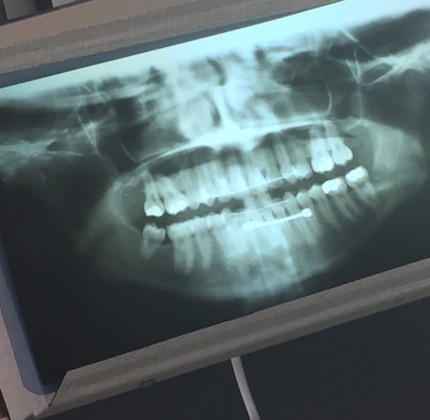

«Похожая история», — написал один из пользователей и прикрепил рентгеновский снимок своей челюсти, где четко видна штанга в языке.